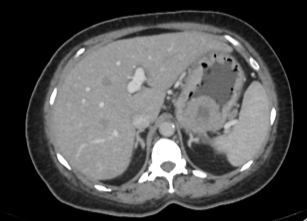

Fibrilação atrial; Dor lombar

Infarto renal.

Opacidade triangular em cunha; realce cortical periférico.